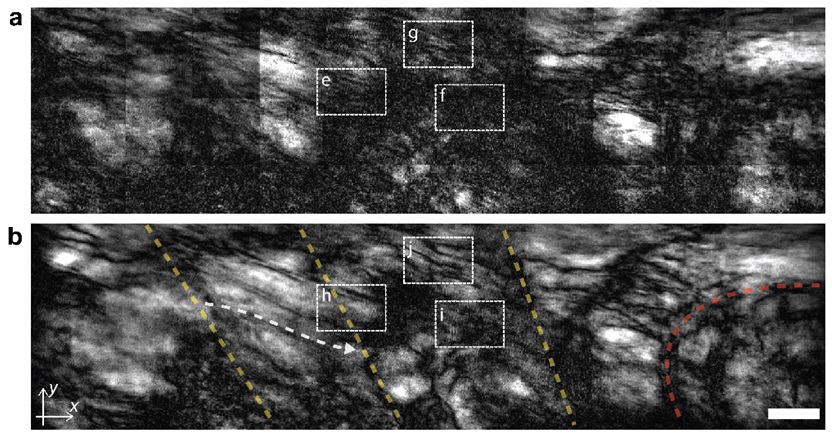

그림 5. 성체 제브라피시 내 근육 관찰 결과

▲ [그림 5] 성체 제브라피시 내 근육 관찰 결과연구진은 일반 광학현미경(a)과 공간게이팅 현미경(b)을 이용해 부화한지 30일 된 성체 제브라피시 내부를 관찰했다. 기존에는 관찰하기 어려웠던 근육중격(노란 점선), 근육-뼈 접합부(붉은 점선), 근육결(흰색 점선)까지 관찰할 수 있음을 볼 수 있다.